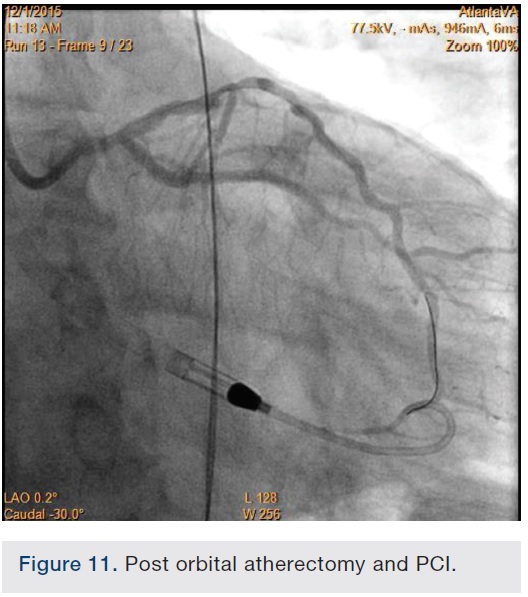

Following successful completion of the peripheral phase, it was felt that a 4-week period was necessary for the iliac stent to heal somewhat (especially since we planned to place a 14 French Cook sheath through it). We then moved on to the coronary phase of this procedure. Bilateral groins and the right wrist were prepared and draped in the usual sterile fashion. Using micropuncture technique with fluoroscopic verification of needle entry into the left CFA at the upper quadrant of the femoral head, a 6 French sheath was placed in the left CFA. The existing left femoral arterial sheath was removed, and the arteriotomy was pre-closed with a single Perclose device (Abbott Vascular). The arteriotomy was then serially dilated with 10, 12 and 14 French dilators, and a 14 French, 30 cm Cook sheath was placed successfully in the left common femoral artery. Following therapeutic anticoagulation with intravenous heparin, a regular J-wire and a 6 French pigtail catheter were used to cross the aortic valve, and the catheter was used to exchange the J wire for the 0.018-inch Platinum Plus wire (Boston Scientific). The Impella CP (3.5) percutaneous left ventricular assist device (LVAD) (Abiomed) was inserted into the left ventricle over the Platinum Plus wire (Figure 8). The Impella was then activated and good flows were verified. Right radial artery access was obtained and a PB 3.0 7.5 French sheathless guide system (Asahi Intecc) was used to engage the left main coronary artery. The LAD was wired uneventfully using a Runthrough wire (Terumo) via a 1.25 x 6 mm over-the-wire (OTW) Sprinter balloon (Medtronic). This was then exchanged for a Viper wire (CSI). Orbital atherectomy of the proximal LAD lesion was performed with excellent results (80,000 rpm x 4 passes, 120,000 rpm x 2 passes) (Figure 9). The LAD wire was then exchanged for a Runthrough wire and the left circumflex (LCX) was wired with a BMW wire. Following plaque modification with orbital atherectomy, predilation of LAD was performed with 3.0 x 20 mm Chocolate Balloon (QT Vascular Ltd) (15 atmospheres x 60 seconds and 15 atmospheres x 30 seconds) (Figure 10) with an excellent result and no dissection (Figure 11). A 3.5 x 38 mm Promus stent (Boston Scientific) (14 atmospheres x 30 seconds) was placed from the left main into the proximal LAD lesion ensuring adequate coverage. The jailed LCX wire was recovered and re-placed in the LCX through the struts of the newly placed LM-LAD stent (Figure 12). Predilation of the LCX ostium was performed with a 2.5 x 8 mm Glider balloon (QT Vascular Ltd) (14 atmospheres x 25 seconds). The mid LAD was stented (ensuring overlap with proximal stent) with 3.0 x 16 mm Promus stent (16 atmospheres x 25 seconds). A final kissing balloon inflation of the LAD/LCX with an NC Sprinter 2.5 x15 mm balloon (Medtronic) into the LCX and a NC Sprinter 3.5 x12 mm balloon into the LAD was performed, with up to 16 atmospheres x 20 seconds on both (Figure 13). Final IVUS of the LM and LAD stent revealed excellent results and the LCX ostium looked excellent as well (Figures 14-16).